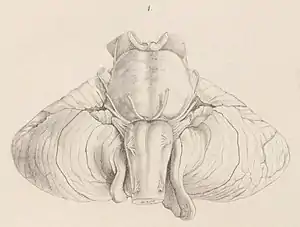

La malformación fue descrita por primera vez en 1883 por el doctor John Cleland, en un artículo titulado Contribution to the study of spina bifida, encephalocele, and anencephalus ("Contribución al estudio de la espina bífida, el encefalocele y la anencefalia") en el Journal of Anatomy and Physiology.[2] Ocho años más tarde, el neurólogo austríaco Hans Chiari escribió un artículo en el Deutsche Medizinische Wochenschriff titulado "Acerca de las alteraciones cerebelosas resultantes de la hidrocefalia cerebral", en el cual reconocía el trabajo de Cleland y añadía su propio sistema de clasificación de este desorden en tipos I, II y III.[3] En 1896, Chiari definió la enfermedad de la siguiente forma: "Una elongación en forma de cuña de las amígdalas cerebelosas y de la parte medial de los lóbulos inferiores del cerebelo, que corren a lo largo de la médula dentro del canal cervical".[4]

Las malformaciones de Chiari consisten en defectos estructurales del cerebelo, órgano encargado de controlar el equilibrio y la coordinación neuromuscular. El cerebelo normal ocupa un espacio indentado en la parte inferior del hueso occipital, encima del foramen magnum, orificio por el cual desciende el extremo del tronco encefálico hacia el canal medular. La malformación de Chiari se produce cuando parte del cerebelo se encuentra ubicado por debajo del foramen.[8]